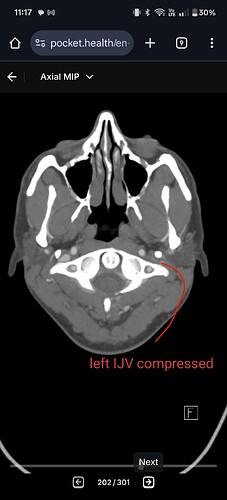

I had discovered that my IJVs are compressed - especially on my left side between my left styloid and C1 transverse process. I also have posterior cervical collateral/compensatory veins on my left side.

This could explain the intracranial hypertension symptoms, but didn’t explain my stroke-like symptoms.

I met with that ENT yesterday. And oh my god, this storm if misery and suffering may be coming to an end. He sat down with me and went through my full imaging. He saw my left greater horn pressing against my ICA. He saw the left IJV compression by the styloid and the posterior collateral veins. I stared complaining that my radiology report stated that my styloids are 3.3cm but the radiologist followed it up by saying they aren’t elongated. I started talking about the definition of ES and he said that don’t worry and that I don’t need to convince him about that. In other words, he knows 3.3cm can be problematic.